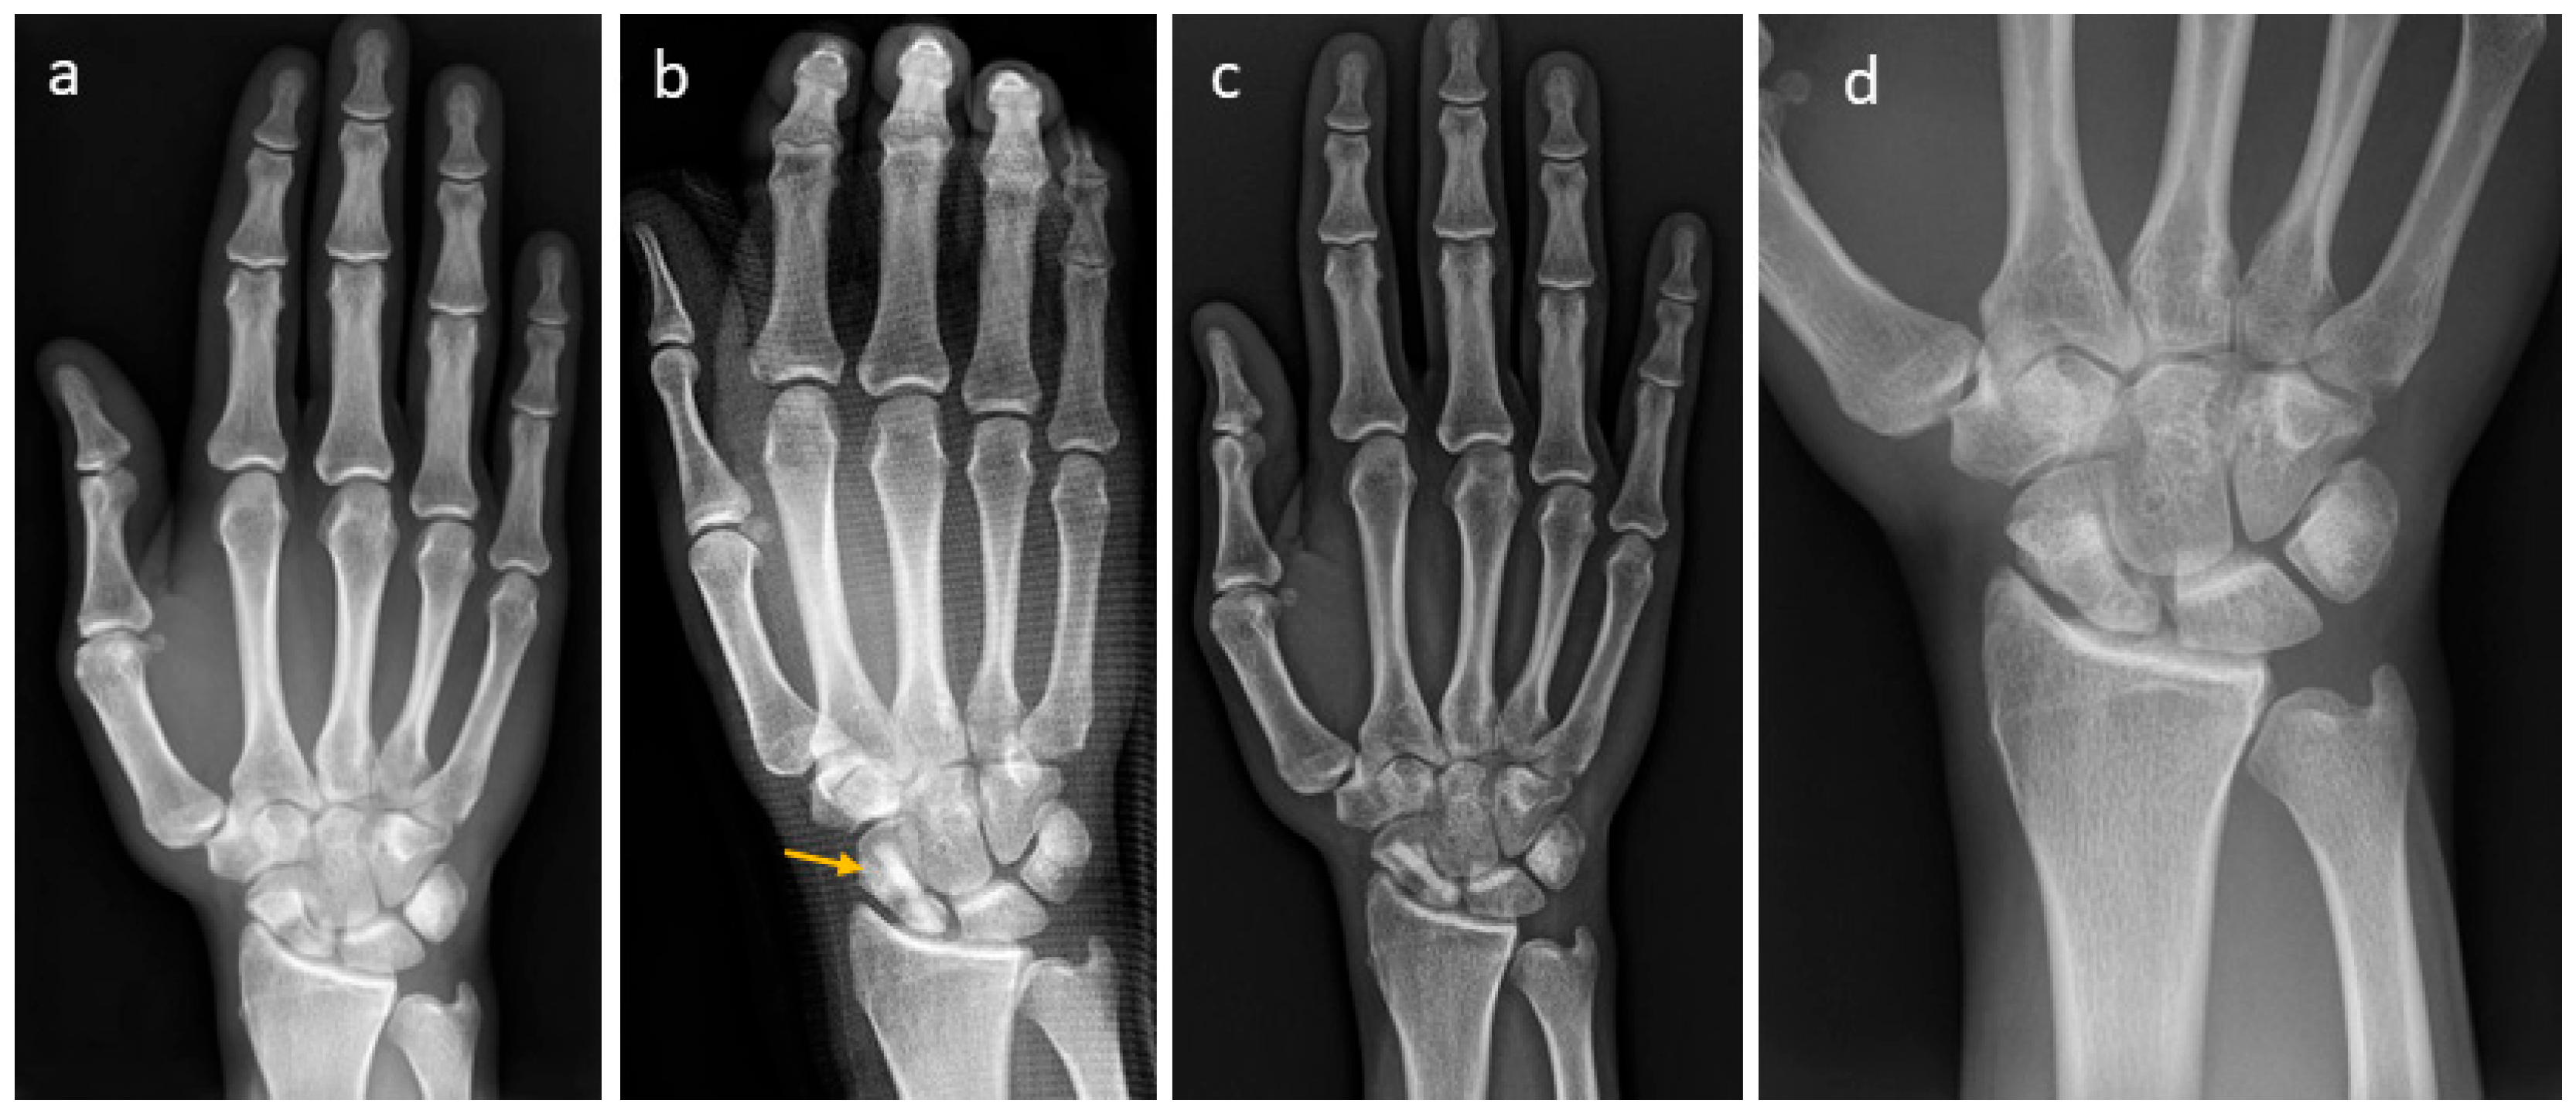

3.4. Selected Case Descriptions